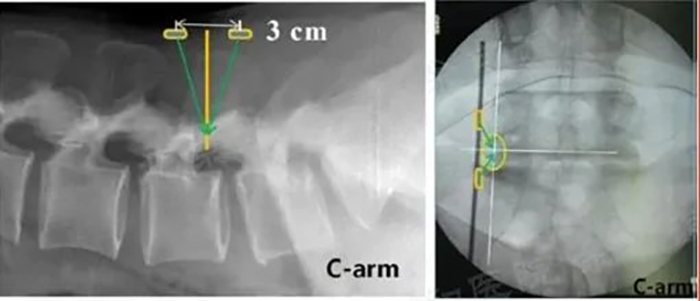

■持取器空心设计,可通过导针。置入过程中,可预先置入导针,依据导针指引置入融合器,也可直接置入融合器。

■体外植骨完成,使用半环工作通道进行神经保护,如直接置入,则融合器直接通过工作通道置入即可;如需导针指引,则预先置入导针,透视导针位置,再沿导针置入融合器。

■透视融合器位置,可用打入器进行调整,如有导针,则拔出导针后再调整。